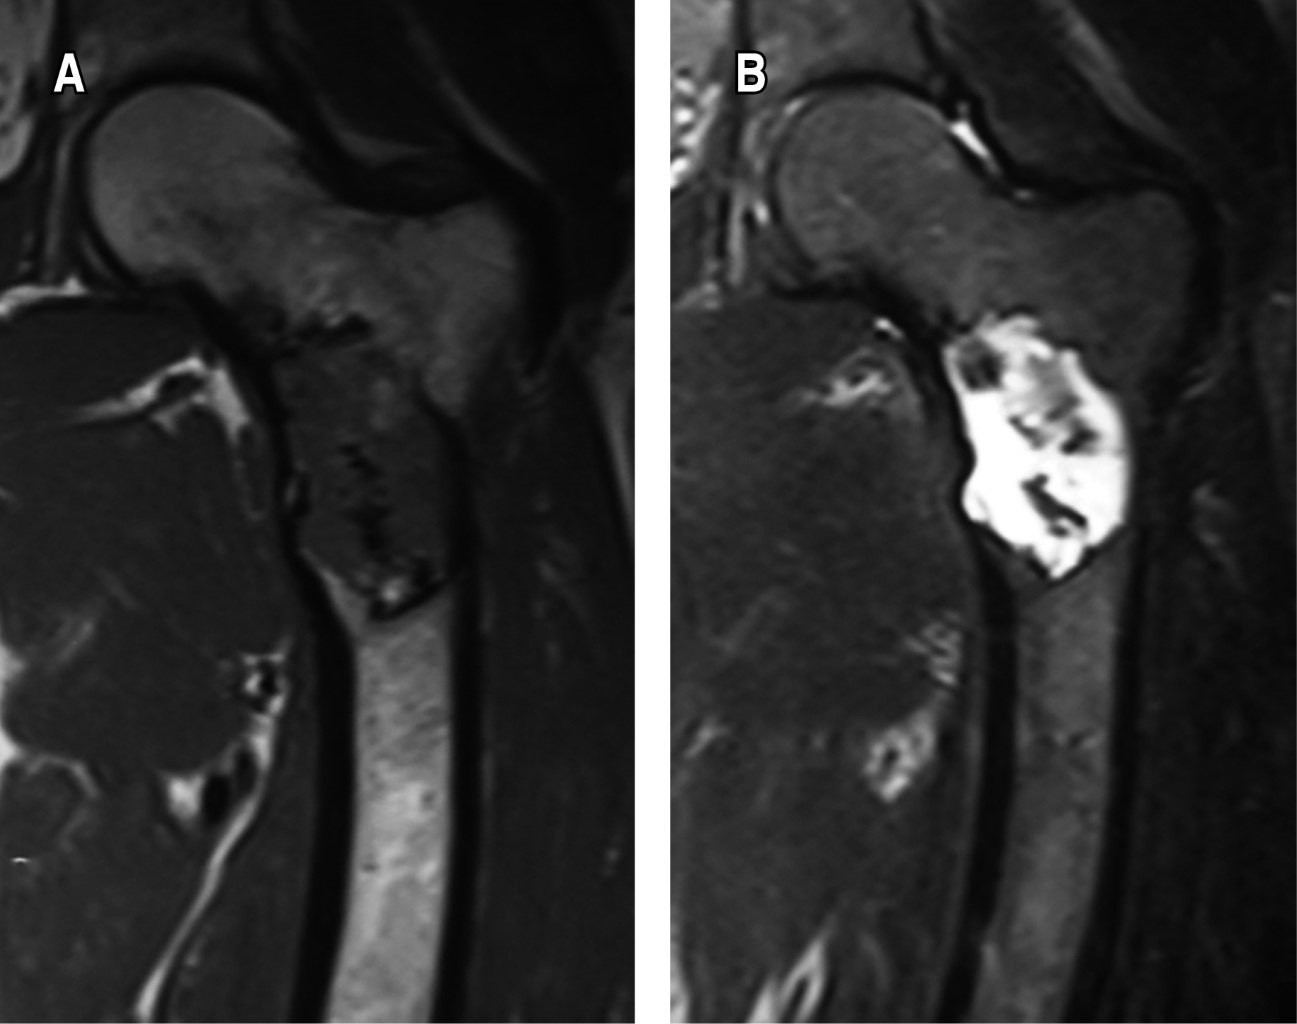

Figure 3